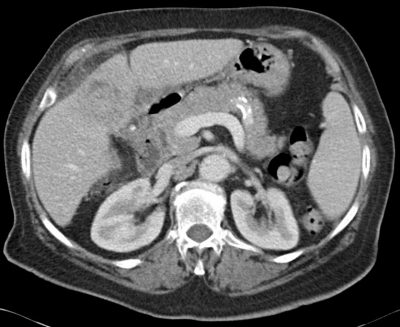

Los estudios por imagen evidenciaban colelitiasis y un proceso que afectaba a la mitad distal de la vesícula infiltrando localmente el lecho vesicular. Fue remitida para cirugía por sospecha de neoplasia. La tomografía axial computada y la resonancia nuclear magnética con colangioresonancia informaron: pérdida del plano de separación con el parénquima hepático y marcados cambios inflamatorios en la grasa adyacente, compatibles con colecistopatía crónica y con proceso inflamatorio agudo, pero sin poder descartar lesión neoplásica subyacente (ver Figuras 1 y 2).

Figura 2: RNM que muestra pared vesicular engrosada, cálculo voluminoso y afectación del lecho vesicular.